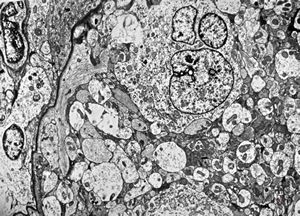

F,49y. | purulent meningitis- meningococcal v.s.

F,49y. | purulent meningitis- meningococcal v.s.

F,49y. | purulent meningitis- meningococcal v.s.